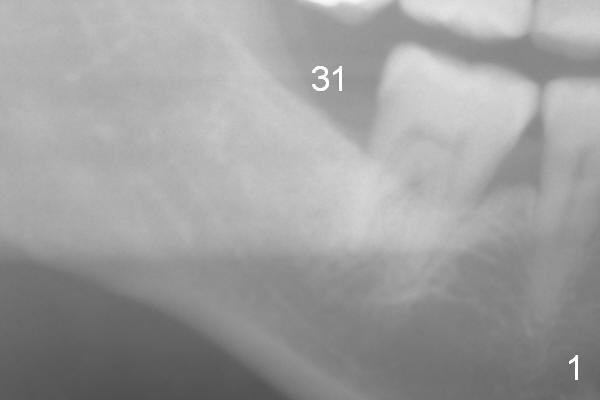

A 59-year-old lady has lost the tooth #31 for several years (Fig.1).  In the last 7 years, the 1st molar has undergone mesial oblique bone loss (Fig.2 *).  The apical half of the lamina dura has become denser (arrowhead).  These 2 types of bone changes suggest occlusal trauma to the tooth, overloading because of missing #31.  The upper 2nd molar appears to have been supraerupted more (Fig.2 black arrow).  Before an immediate provisional is fabricated for the tooth #31, a short abutment is expected (possible 5841 or 6841).

Since panoramic X-ray does not show the nerve very well (Fig.1,2 yellow dashed line), a PA should be taken prior to surgery, as deep as possible.  If the PA does not work, CT will be taken.

The buccolingual ridge should not be too wide.  #15 is expected.  For safety, an implant system with stoppers will be used for the area with poor visibility.  Distance from the neighboring tooth is 5 mm (Fig.2 red lines).  Set the 4 mm implant spacer with 2 mm pilot drill.